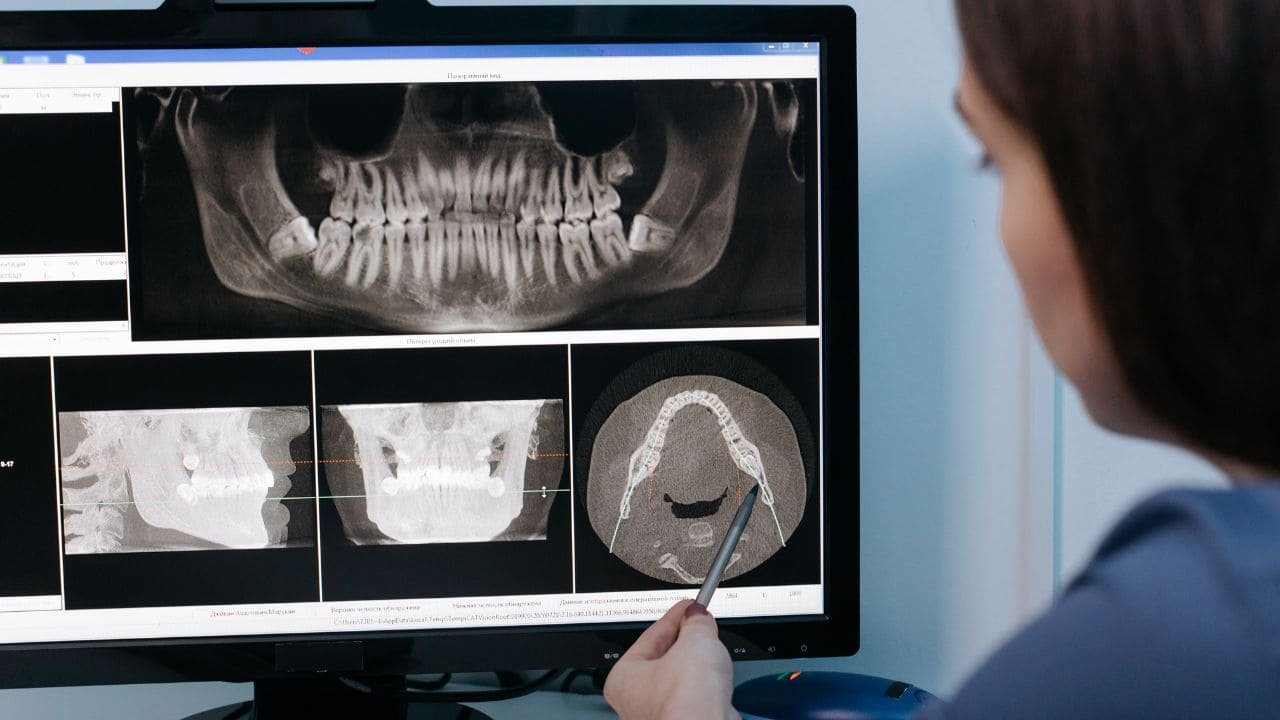

Critères radiologiques

Le critère radiologique est le plus fiable pour évaluer la correction d’un décalage squelettique. Il permet de vérifier les résultats du traitement et de confirmer le retour à un équilibre architectural. Des téléradiographies doivent être réalisées avant, pendant (après amélioration clinique) et en fin de traitement. La superposition des tracés permet de contrôler l’efficacité du traitement, le siège et l’ampleur des améliorations.

La radiographie panoramique en fin de traitement est essentielle pour visualiser les axes dentaires (parallélisme des racines), détecter les courbures apicales iatrogènes ou les résorptions radiculaires. Dans les cas de dysharmonie dento-maxillaire (DDM) traitée en denture adolescente, l’évaluation radiologique de l’espace disponible pour l’éruption des dents de sagesse est impérative pour éviter la récidive.